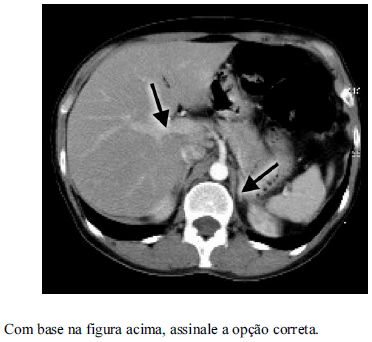

Em um exame de tórax, uma imagem tomográfica é documentada com janela de cerca de 1600 UH e nível de aproximadamente 600 UH. Nesse caso, o técnico em radiologia pretende demonstrar para avaliação a estrutura anatômica